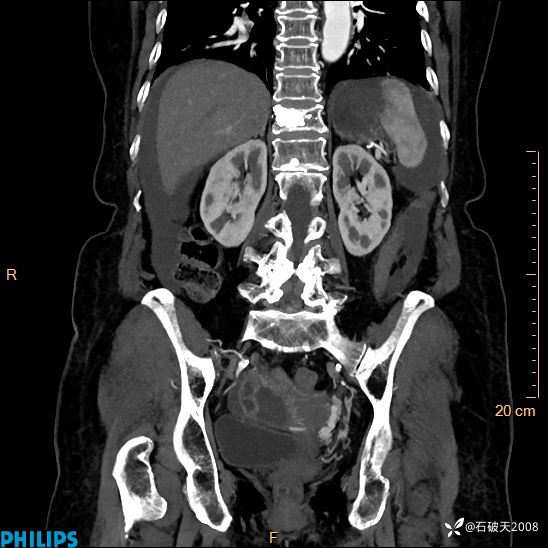

平扫